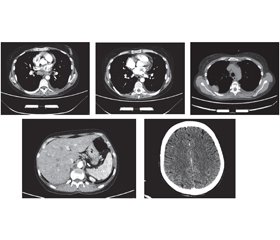

Актуальність. Щороку в усьому світі кількість людей із рідкісними формами хвороб збільшується. Однією з них є катастрофічний антифосфоліпідний синдром — синдром Ашерсона. На сьогодні він активно досліджується, однак патофізіологічні механізми його розвитку ще не вивчені до кінця. Наша робота є першою спробою опису синдрому Ашерсона на прикладі клінічного випадку в Україні. Мета: визначення факторів і механізмів, що призвели до смертi пацієнта з синдромом Ашерсона в Україні. Матеріали та методи. Під час роботи використані структурно-логічний аналіз і клініко-статистичний метод. Результати. На основі комплексу клінічних і лабораторних критеріїв наша медична група поставила пацієнту клінічний діагноз системного червоного вовчака, ускладненого катастрофічним антифосфоліпідним синдромом. Незважаючи на лікування глюкокортикоїдами та антикоагулянтами відповідно до міжнародних рекомендацій, пацієнт помер. Результати розтину показали, що безпосередньою причиною смерті став великий тромб, який закупорював легеневу артерію та її основні гілки. При гістологічному дослідженні було виявлено тромбоз дрібних судин нирок і мозку, підозрювали нейроендокринну пухлину (G2; pT3pNxpM1b) тонкої кишки з метастазами в печінку, мозок, міокард та нирки. Для уточнення гістологічного діагнозу було проведене додаткове імуногістохімічне дослідження. Морфологічна картина і результати імуногістохімічного дослідження найбільше відповідають помірно диференційованому (G2) незроговілому плоскоклітинному раку (код МКХ-О: 8070/3) із пошкодженням стінок тонкої кишки, печінки, легенів, нирок, міокарда та мозку. Висновки. Наведені дані підкреслюють, що, незважаючи на рідкість синдрому Ашерсона, завжди необхідно враховувати його ймовірність у разі ознак множинного тромбозу та поліорганної недостатності. Оскільки його розвиток є наслідком серйозних захворювань, серед яких захворювання сполучної тканини, злоякісні утворення, інфекції, етіотропне та патогенетичне лікування може запобігти розвитку катастрофічного антифосфоліпідного синдрому та смерті.

Background. Every year, the number of people with rare forms of the disease is increasing worldwide. One of these is the catastrophic antiphospholipid syndrome — Asherson’s syndrome. To date, it is being actively studied, but the pathophysiological mechanisms of its development have not yet been fully investigated. Our work is the first attempt to describe Asherson’s syndrome on the example of a clinical case in Ukraine. Objective: to determine the factors and mechanisms that led to the death of a patient with Asherson’s syndrome in Ukraine. Materials and methods. The structural-logical analysis and the clinical-statistical method were used. Results. Based on clinical and laboratory criteria, our medical team established a clinical diagnosis of systemic lupus erythematosus complicated by a catastrophic antiphospholipid syndrome (CAPS). Despite treatment with glucocorticoids and anticoagulants according to international guidelines, the patient died. The autopsy results showed that the immediate cause of death was a large blood clot that blocked the pulmonary artery and its main branches. Histological examination revealed thrombosis of small vessels of the kidneys and brain; a neuroendocrine tumor (G2; pT3pNxpM1b) of the small intestine with metastases to the liver, brain, myocardium and kidneys was suspected. An additional immunohistochemical study was performed to clarify the histological diagnosis. The morphological picture and results of immunohistochemical study mostly correspond to the moderately differentiated (G2) non-keratinizing squamous cell carcinoma (ICD-O code: 8070/3) with damage to the walls of the small intestine, liver, lungs, kidneys, myocardium and brain. Conclusions. These data emphasize that despite the rarity of Asherson’s syndrome, it is always necessary to consider its probability in the presence of signs of multiple thrombosis and multiple organ failure. Because its development is the result of serious diseases, including connective tissue diseases, malignancies, infections, the etiotropic and pathogenetic treatment can prevent the development of CAPS and death.